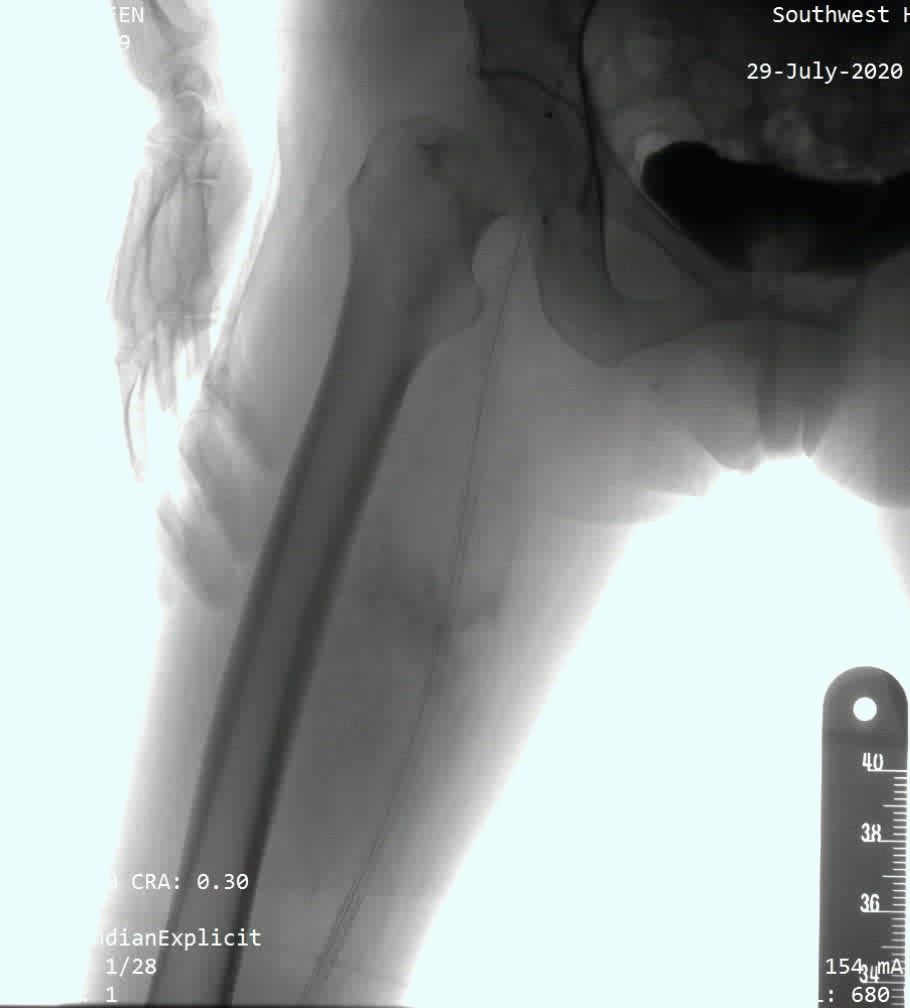

病例1:为股浅长段闭塞病变,术者采用了knuckle技术,选择Command 18导丝顺利通过病变。